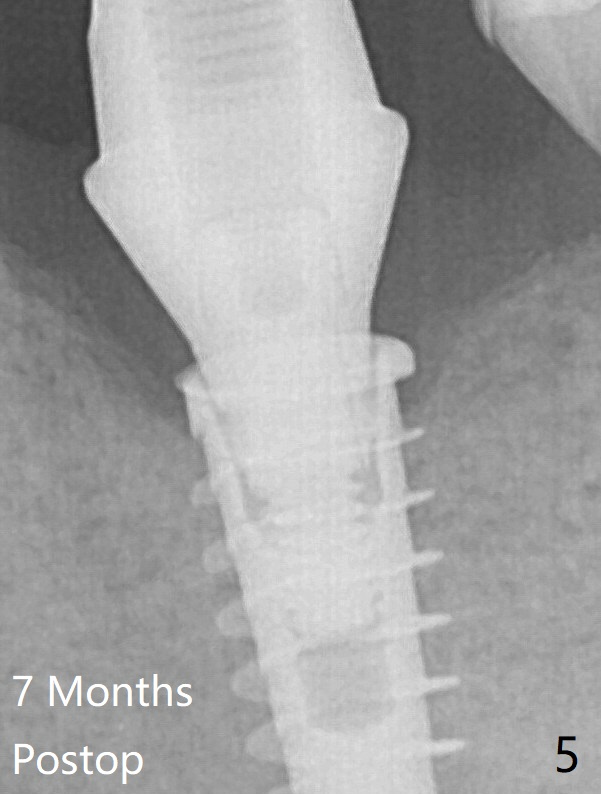

Due to the narrow ridge, a 4.5x11 mm implant is placed (Fig.4); before as well as after placement of a 6x4(3) mm abutment, the mesial socket (*) is filled with Vera graft and autogenous bone as well as collagen plug. Following suturing, periodontal dressing is applied to the wound. There is no apparent bone loss 7 months postop (Fig.5) or 14 months post cementation (Fig.7). In fact the abutment has been incompletely seated, which may be related to #13 failure. The bone density of the crest appears to increase with function.